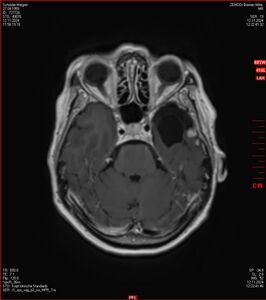

MRT vom 12. November 2024

So nun ein paar neue Bilder aus meinem Kopf. (Durch klicken bekommt man eine größe Ansicht eines Einzelbildes).

Die letzten drei Bilder Zeigen aus meiner Sicht den Tumor, der im Jahr 2021 bestrahlt wurde.